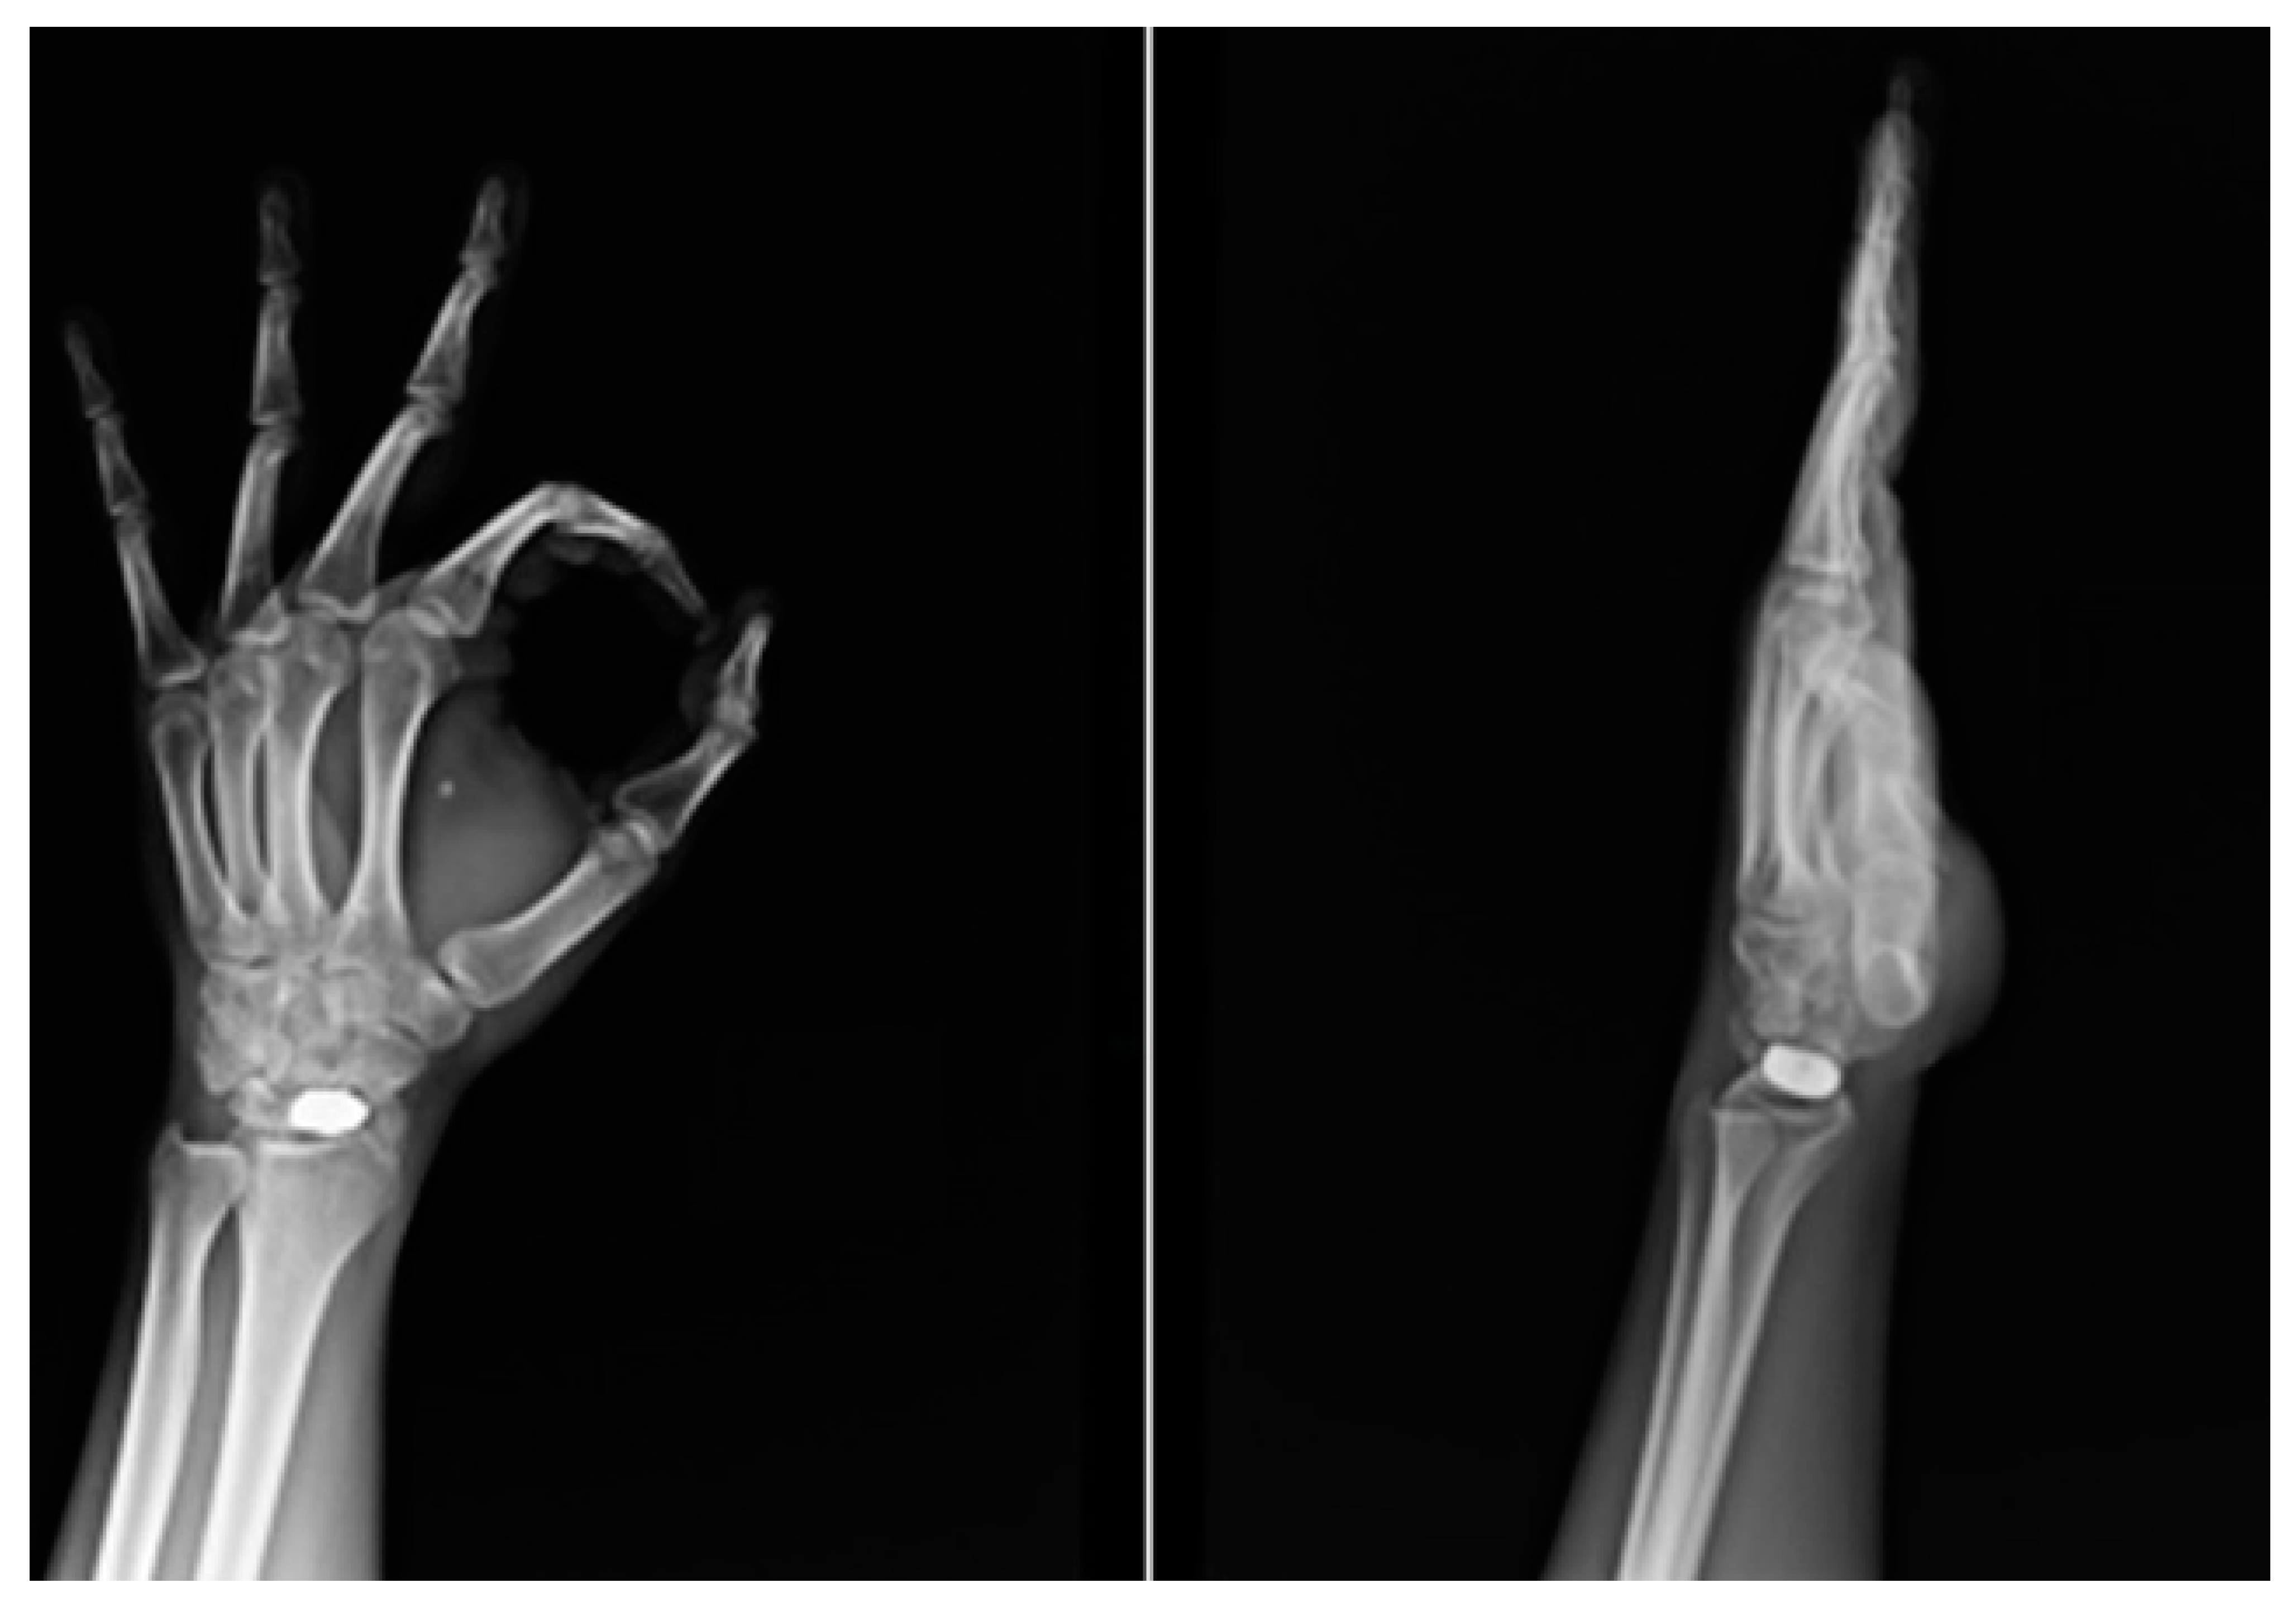

2.4. Surgical Technique